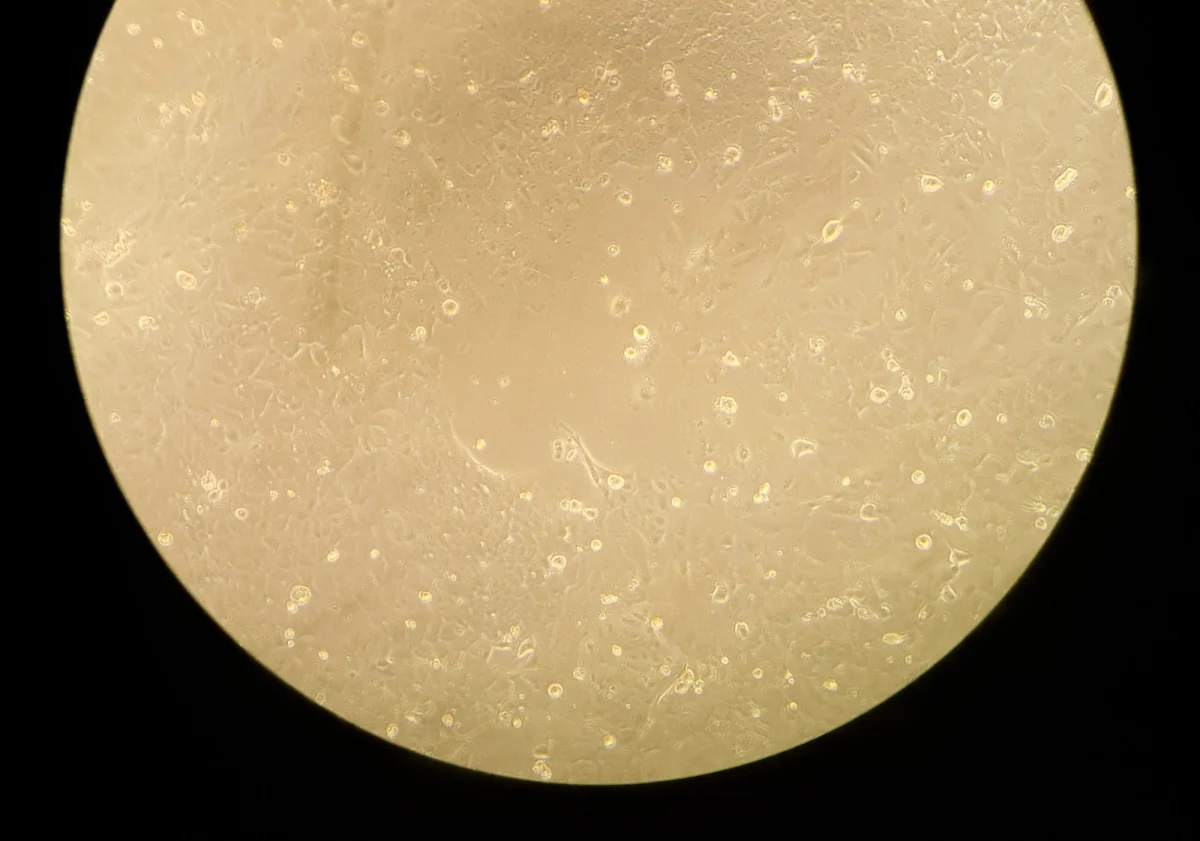

Podobno taki obrazek to tradycja:

Hodowane przeze mnie komórki nowotworowe widziane pod mikroskopem z obrazka wyżej: